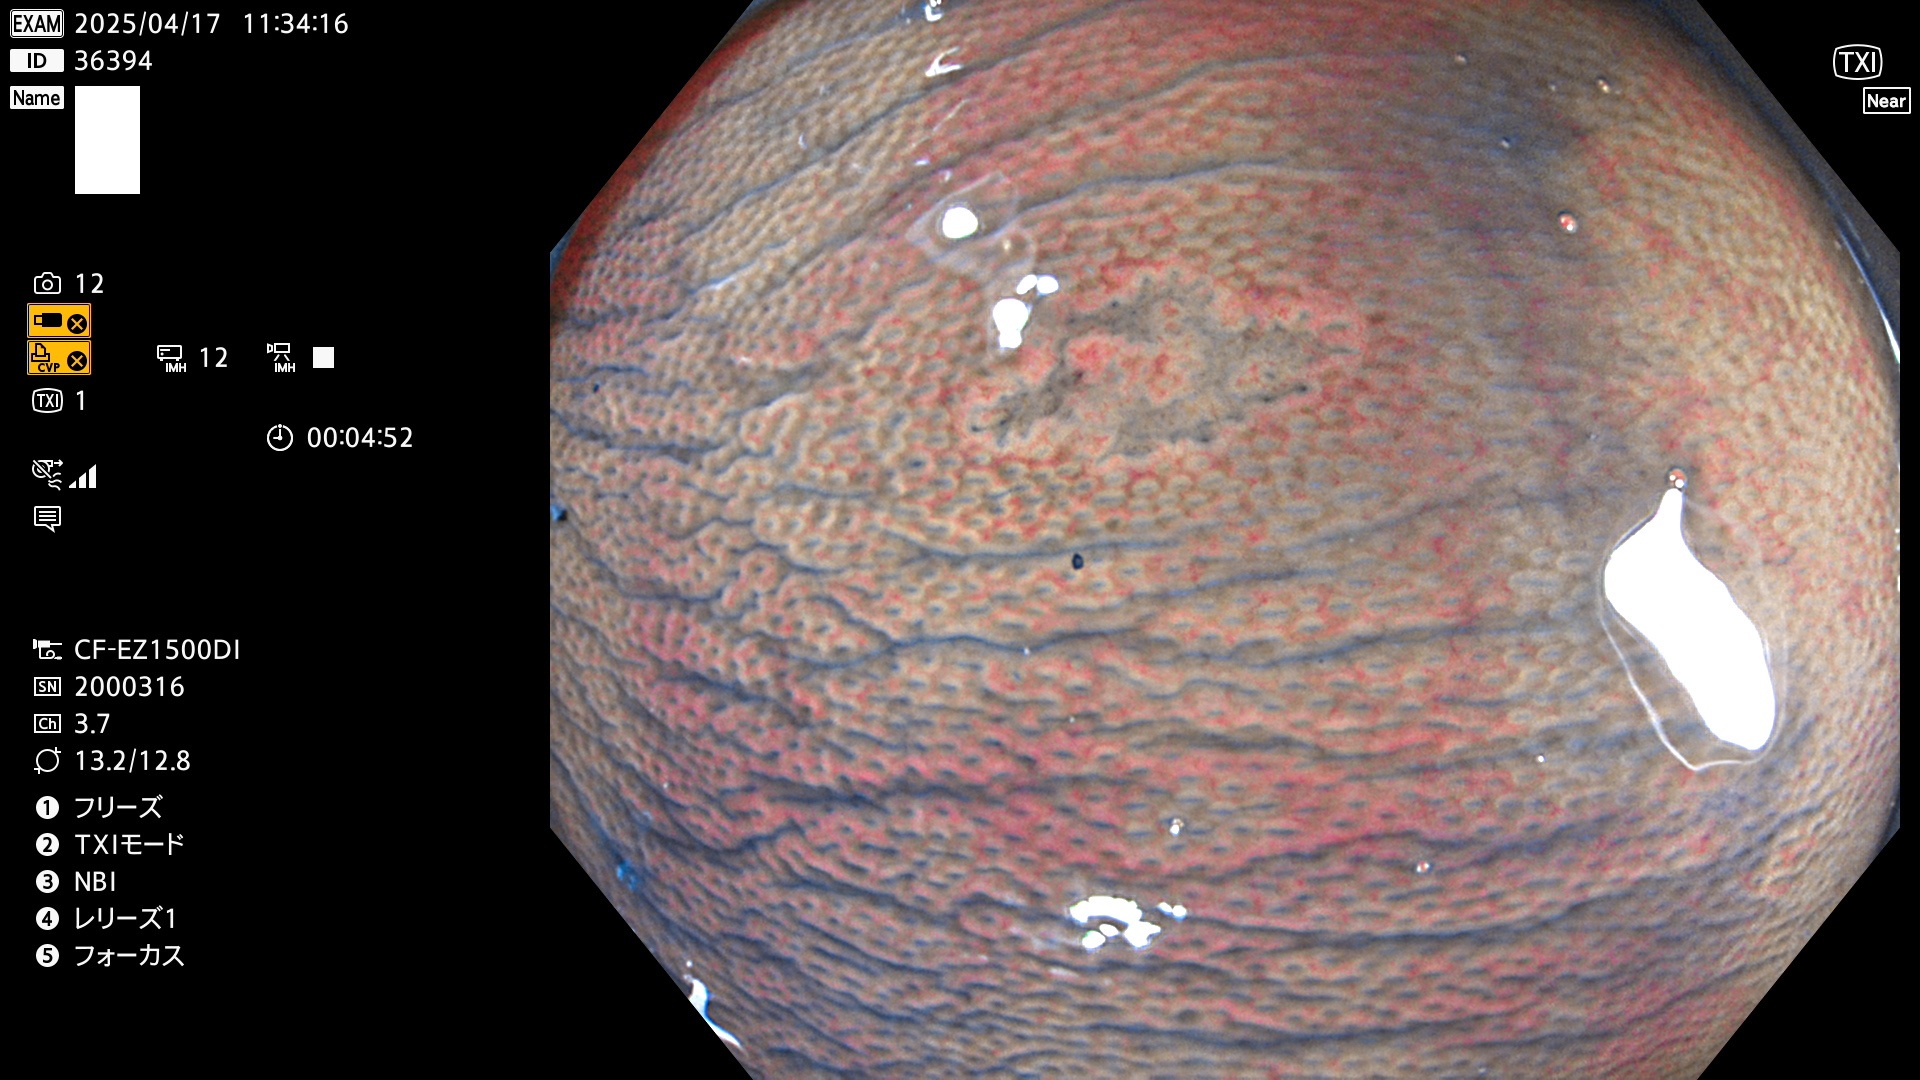

今週のUb、Uc型腺腫

完全に平坦な物をUb、陥凹している物をUcと呼びます。Ubは認識が困難で、Ucはびらん(炎症)と紛らわしいために見落とされやすく、「内視鏡後・大腸癌」の原因になります。

毎週の検査(木・金・土・日)に発見されたUb、Uc型・腺腫を、その週の日曜の夜にUPし1週間、提示します。

抽出の対象期間 2025年4月17日〜4月20日の4日間(48件の検査)8個 (8/48=16%)